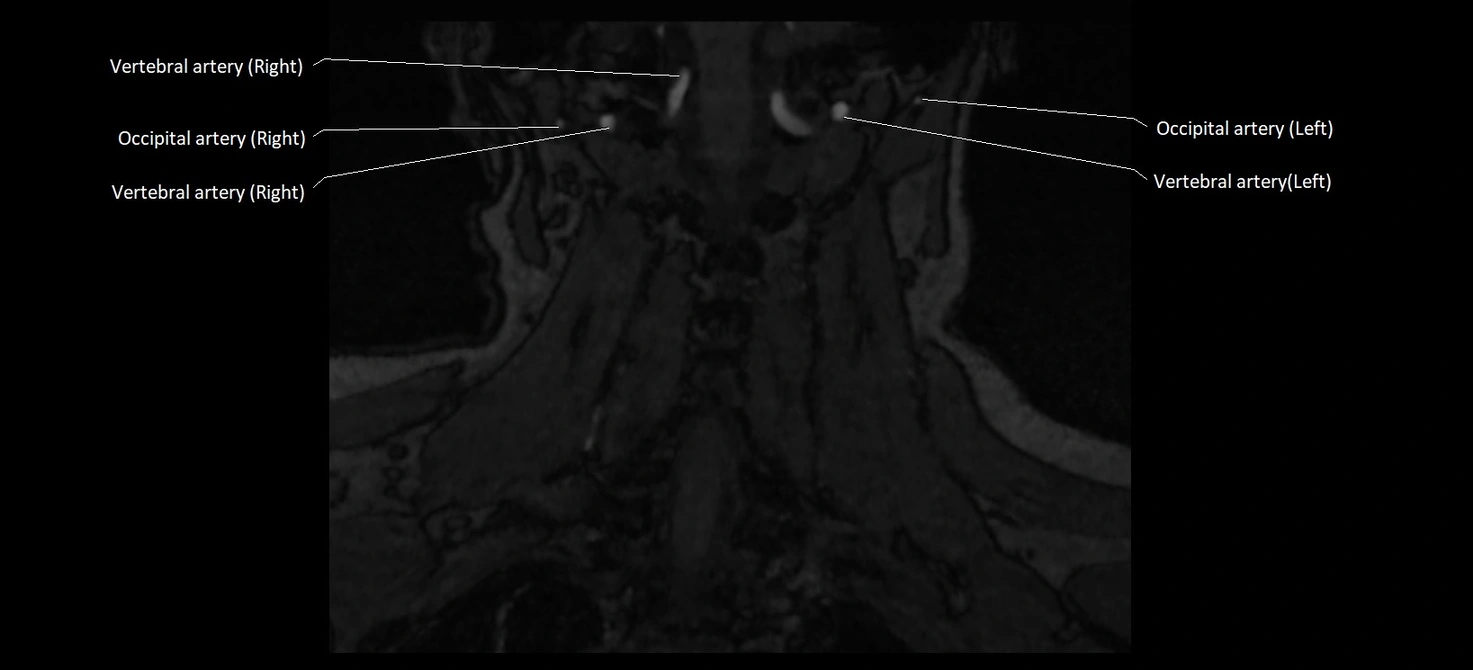

MRI images

image